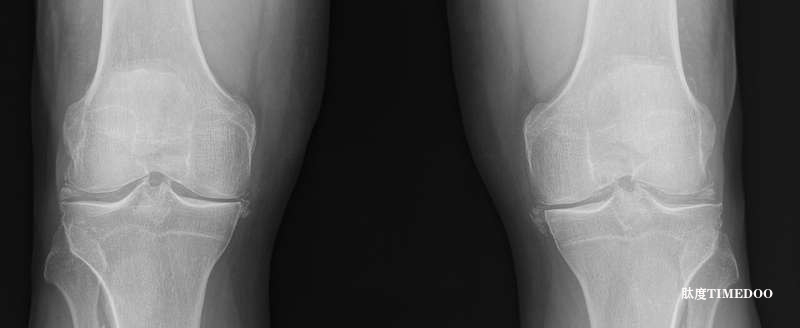

鈣焦磷酸鹽沉積病是一種由鈣焦磷酸鹽(CPP)晶體沉積在關(guān)節(jié)組織中引起的異質(zhì)性結(jié)晶性關(guān)節(jié)炎,常導(dǎo)致急性或慢性的關(guān)節(jié)癥狀。60歲以上人群中,CPPD是最常見的炎性關(guān)節(jié)炎類型之一。

研究數(shù)據(jù)顯示,在歐美地區(qū),約10%的中年人存在影像學(xué)證據(jù)提示CPPD,80歲以上人群的發(fā)病率更升高至30%左右。CPPD與軟骨退變和骨關(guān)節(jié)炎密切相關(guān),但目前尚不清楚其為因或果。

CPPD最廣為人知的表現(xiàn)是急性CPP晶體關(guān)節(jié)炎(俗稱“假痛風(fēng)”),其發(fā)病機制為CPP晶體在關(guān)節(jié)內(nèi)激活促炎通路,誘導(dǎo)IL-1β分泌,從而引發(fā)急性炎癥反應(yīng)。影像學(xué)上,軟骨鈣化(chondrocalcinosis)在老年人中常見,且每增加10歲,其患病率幾乎翻倍。